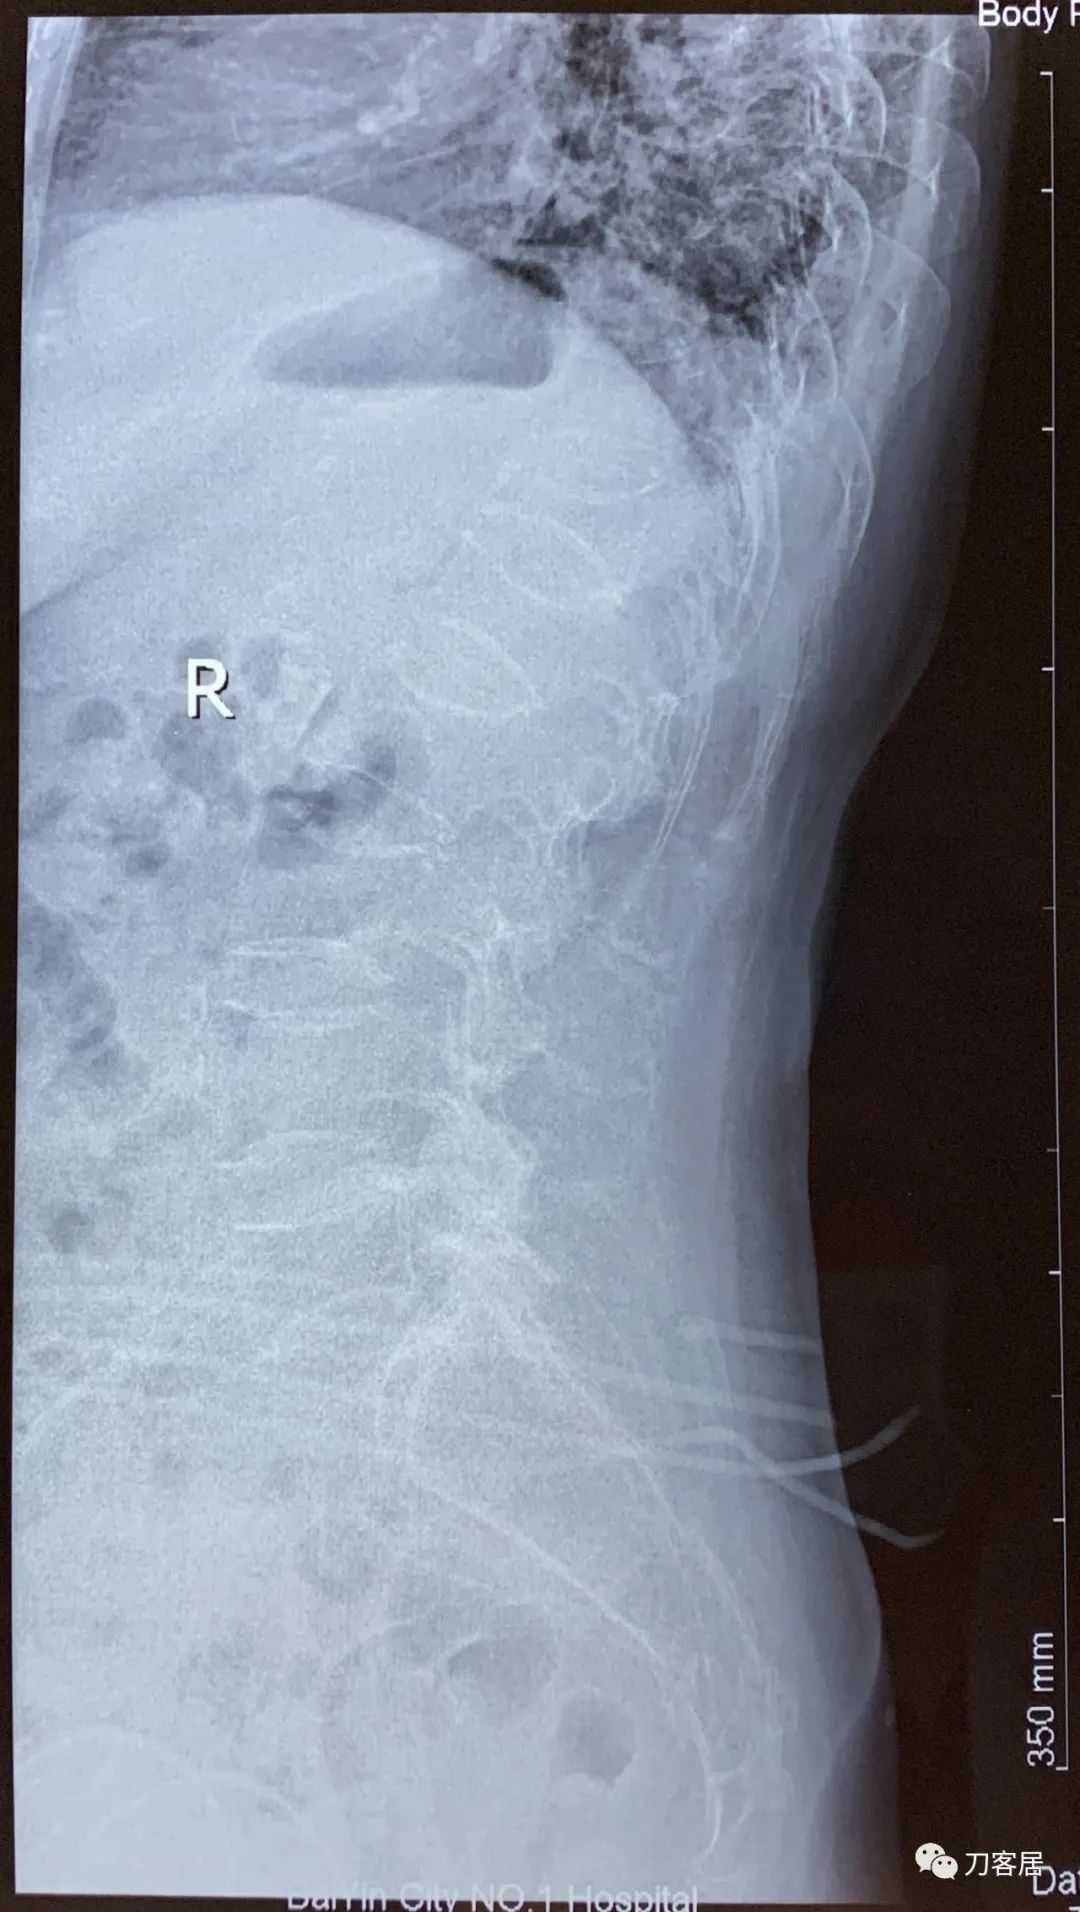

自带影像学资料提示胸椎,腰椎多发脊柱压缩性骨折。

诊断 : 重度骨质疏松症,胸椎、腰椎多发椎体压缩性骨折

图04-20200825腰椎侧位X线片